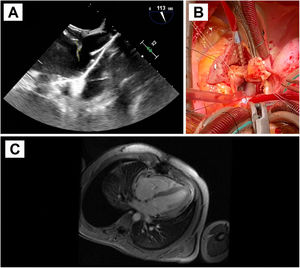

Caso clínico 1Se presenta un caso clínico de un hombre de 52 años con antecedentes de hipertensión arterial, hipercolesterolemia, migraña y adenocarcinoma de colon intervenido libre de enfermedad. Se detectó un FOP como estudio etiológico de un ictus isquémico en territorio de la arteria cerebral media derecha, llevándose a cabo su cierre percutáneo por vía venosa femoral con un dispositivo de 24 mm, sin complicaciones. Tres años después, el paciente presentó un síndrome febril con hemocultivos positivos para Staphylococcus aureus meticilín-sensible, por lo que se inició tratamiento con cloxacilina y daptomicina. En la ecocardiografía transtorácica no se apreciaron hallazgos patológicos, pero en la ecocardiografía transesofágica se objetivó una masa móvil de gran tamaño anclada a la vertiente auricular izquierda del dispositivo de cierre de FOP, con protrusión hacia la válvula mitral, compatible en ese contexto con vegetación endocardítica (fig. 1A). Se decidió cirugía urgente por el gran tamaño de la masa, bajo circulación extracorpórea y con pinzado aórtico. Se procedió a la resección del dispositivo de cierre de FOP que presentaba un absceso adherido en la vertiente auricular izquierda. Existía una endotelización incompleta del mismo (fig. 1B). Posteriormente, se reconstruyó el septo interauricular con parche de pericardio heterólogo. La evolución postoperatoria del paciente fue satisfactoria, terminando antibioterapia ambulatoria1.

A: Ecocardiografía transesofágica preoperatoria. Se aprecia la masa de gran tamaño anclada al dispositivo de cierre de FOP, en la vertiente auricular izquierda, que protruye hacia la válvula mitral. B: Fotografía del campo quirúrgico. Atriotomía derecha para acceso al septo interauricular donde se encuentra anclado el dispositivo de cierre de FOP, con endotelización incompleta. Resección del dispositivo objetivándose en la vertiente auricular izquierda un absceso adherido.